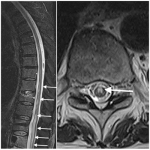

INSTRUCCIÓN ORTOPÉDICA DE POSGRADO – IMÁGENES

Resolución del caso

Pedro L. Bazán, Arles Pérez Gutiérrez, Alin L. Garay